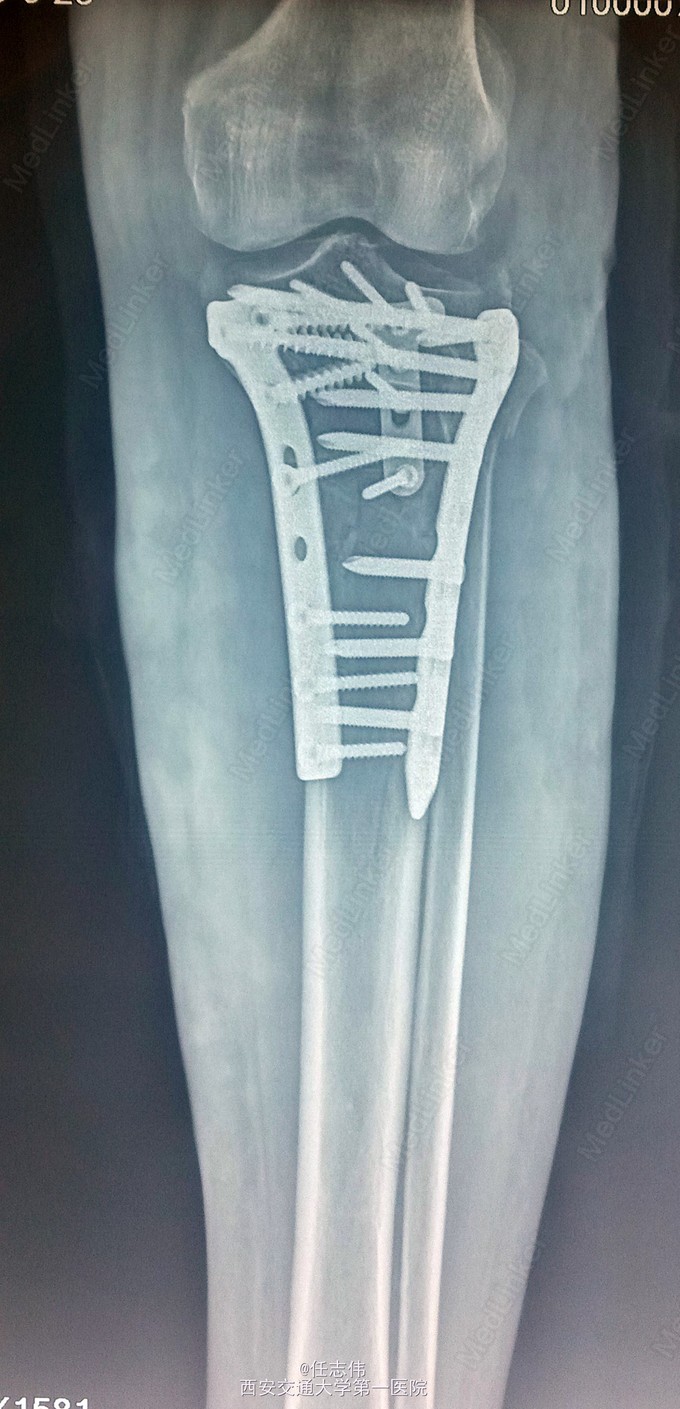

女性,66岁,摔伤致左膝部疼痛活动受限7天 7天前摔伤致左膝部疼痛伴活动受限,在当地医院行跟骨牵引、消肿对症治疗7天,已基本消肿,足部感觉、活动、血供正常。 既往有糖尿病史。

左膝关节周围肿胀,胫骨平台处压痛明显,外侧为著,膝关节活动受限。左足背动脉搏动好,踝及足趾感觉活动正常。

诊断:右胫骨平台骨折 处理:骨折切开复位内固定术。行内外侧入路钢板固定,术中行外侧平台塌陷复位,髂骨植骨内固定。另因考虑有后柱骨折,遂行后外侧切口,支撑钢板固定。术中见患者骨质疏松明显。 术后伤口愈合好,局部仍肿胀明显。